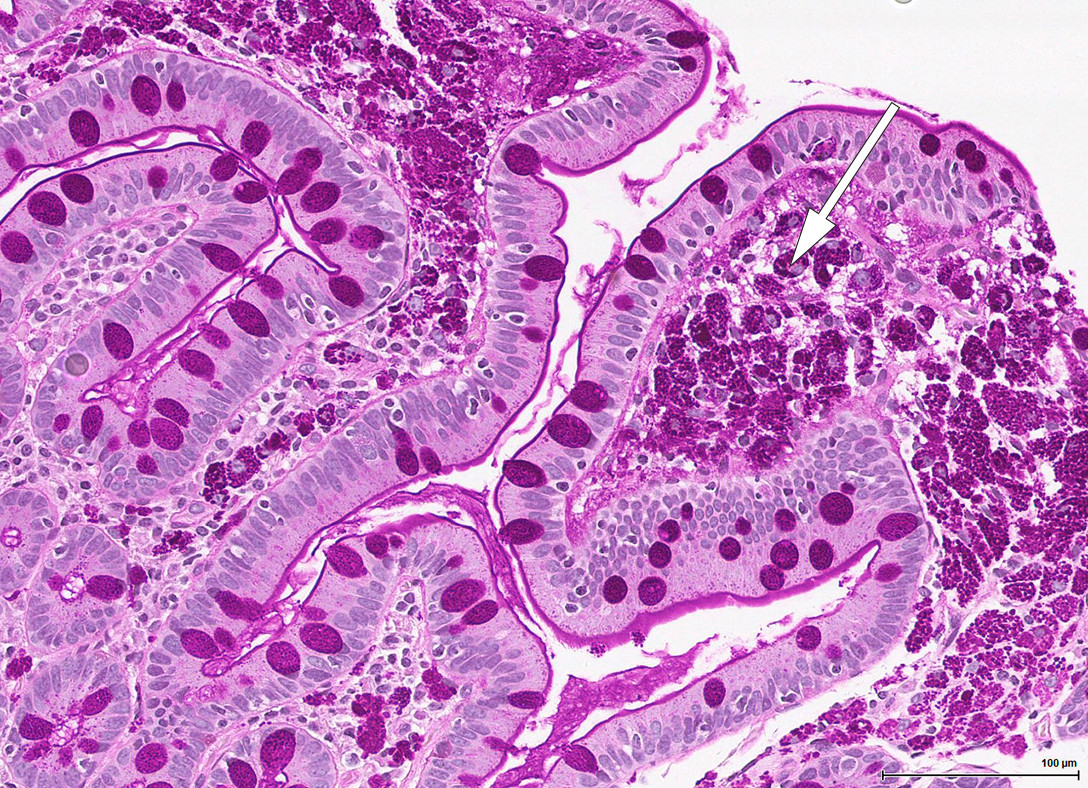

Konstellasjonen av migrerende leddsmerter og synovitter over flere år uten utvikling av radiologiske artrittforandringer, kombinert med intermitterende diaré og proteintapende enteropati gjorde at vi mistenkte Whipples sykdom, en sjelden infeksjonssykdom forårsaket av den grampositive bakterien Tropheryma whipplei. Pasienten ble henvist til gastroskopi og kapselendoskopi av tynntarm som viste betydelig inflammasjon med erosjoner, hemoragiske slimhinner og diffus lymfangiektasi (fig 2) (fig 3). Duodenalbiopsier viste breddeøkte totter og akkumulering av skummakrofager med periodisk syre-Schiff (PAS) diastasepositive granulære inklusjoner i cytoplasma (fig 4) (fig 5). Både de makroskopiske og histopatologiske funnene var godt forenlig med Whipples sykdom. PCR utført etter DNA-ekstraksjon fra parafininnstøpt tarmbiopsi var positiv for T. whipplei for to separate målgener (varmesjokkprotein og 16S rRNA). Sekvensering av 16S rDNA PCR-produktet bekreftet T. whipplei. Pasientens ikke-destruktive seronegative artritt, diaré, malabsorpsjon og utmattelse ble antatt å representere manifestasjoner av Whipples sykdom. Iskemiske slag og lungeembolier er beskrevet hos pasienter med Whipples sykdom, og sykdommen representerte en plausibel årsak til pasientens hittil uforklarlige trombosetendens (1),( 2).

Klassisk Whipples sykdom diagnostiseres på bakgrunn av øvre endoskopi, duodenalbiopsier og PCR-undersøkelse. Gastroskopi kan vise ødematøse slimhinner med erosjoner og lymfangiektasi. Lymfangiektasien skyldes akkumulering av makrofager i lymfekarene, med resulterende lymfestase. Allikevel er det viktig å være klar over at de fleste pasientene har makroskopisk normal tynntarmsslimhinne, så biopsier anbefales selv ved upåfallende gastroskopi (5). Multiple biopsier øker sensitiviteten (6). Kapselendoskopi av tynntarm kan brukes for å kartlegge sykdomsutbredelsen. Mikroskopering av duodenalbiopsi viser akkumulering av skummakrofager med PAS-positive intracellulære inklusjoner. Det PAS-diastase-positive materialet svarer til bakteriekapselen som inneholder mykopolysakkarider. Andre årsaker til PAS-positive makrofagansamlinger i tynntarm er blant annet mykobakterieinfeksjon, avleiringssykdommer og langerhanscelle-histiocytose. Disse differensialdiagnosene kan avkreftes med tilleggsundersøkelser.